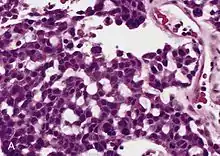

![]() Micrografía de un carcinoma adrenocortical (a la izquierda de la imagen, azul oscuro) y de la corteza adrenal de la que surgió (arriba a la derecha de la imagen, rosa / azul claro). La médula suprarrenal benigna está presente (mitad derecha de la imagen, gris/azul). Tinción H&E. | ||

Los tumores suprarrenales a menudo no se biopsian antes de la cirugía, por lo que el diagnóstico se confirma al examinar la muestra quirúrgica por un patólogo. En general, los carcinomas adrenocorticales a menudo son grandes, con una superficie de corte de color canela y áreas de hemorragia y necrosis. En el examen microscópico, el tumor generalmente muestra láminas de células atípicas con cierta semejanza con las células de la corteza suprarrenal normal. La presencia de invasión y actividad mitótica ayuda a diferenciar cánceres pequeños de adenomas adrenocorticales. Hay varias variantes relativamente raras de carcinoma corticoadrenal: